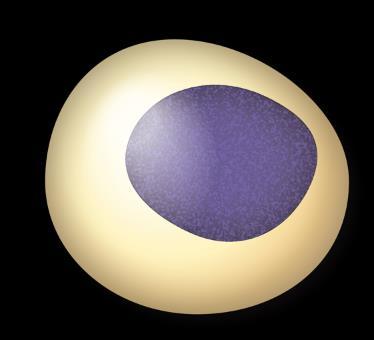

Myeloma Is a Cancer of Plasma Cells

Bone Marrow of a Patient With MM

15

RA, et al. Mayo Clin Proc. 2003;78:21-33.

MM = multiple myeloma. Kyle

Image courtesy of American Society of Hematology

Plasma Cells Are Differentiated B Cells That Produce Antibodies

B-cell malignancies have characteristics similar to the stages of B-cell development FDC

Multiple myeloma (MM)